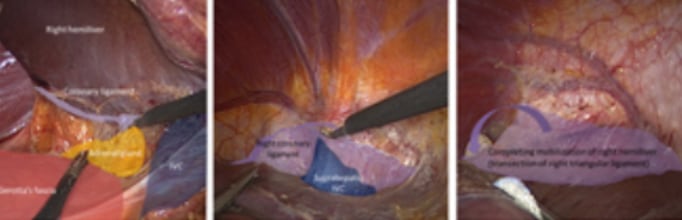

2. Semiprone offers a good view for right hemiliver mobilization

3. When the right hemiliver is mobilized, the right lobe slips to the left due to gravity and a large working space is created under the right side of the diaphragm. This large working space is in contrast to the small subphrenic space seen when a patient is positioned in supine position

4. In supine position the cutting plane between the anterior and posterior sectors of the liver is horizontal and gravity obstructs the exposure of the cutting plane in the small subphrenic space which causes difficulties in bleeding control. However, in semiprone position the cutting plane becomes more vertical

Supine

Semiprone